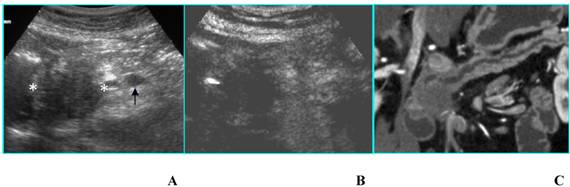

a) Ductal adenocarcinoma is usually hypoechoic (absent or poor enhancement compared to normal pancreatic parenchyma), because of its scanty vascularization [2] (Fig. 1). In particular, tumors in which the size of the hypoechoic area is unchanged on CEUS have clear margins with no infiltration or inflammation; tumors in which the size of the hypoechoic area is reduced on CEUS have blurred margins with infiltration of cancerous cells and inflammation. CEUS may be a tool for evaluating pathologic changes of pancreatic cancer and may provide useful information in the pre-treatment phase [2].

Fig 1

Adenocarcinoma in a 85-year-old woman who presented with diabetes at sudden onset. A. B-mode US (transverse scan) shows a hypoechoic mass, located in the head of the pancreas (asterisks), 3.5 cm in diameter. Splenic vein (arrow) is visible. B. On CEUS the mass is hypoechoic (asterisks) compared to the surrounding parenchyma in the arterial phase. C. MDCT curved reformatted image depicts pancreatic duct dilatation and hypodense lesion in the head of the pancreas.

Ductal adenocarcinoma is rarely isoechoic (enhancement similar to normal pancreatic parenchyma); this pattern is due to a moderate vascularization (Fig. 2) occurring in some histotypes (anaplastic carcinoma and acinar cell carcinoma) [3]. The isoechoic pattern is often observed in focal pancreatitis too [4]: therefore, CEUS is not always able to accurately differentiate adenocarcinoma from focal pancreatitis, as well as CT and MR [5].

Fig 2

Adenocarcinoma in a 45-year-old woman who presented with jaundice. A. B-mode US (trasverse scan) shows a hypoechoic mass in the head of the pancreas, 4 cm in diameter. Main pancreatic duct dilatation (arrow) is visible. B. On CEUS the mass is isoechoic in the arterial phase.